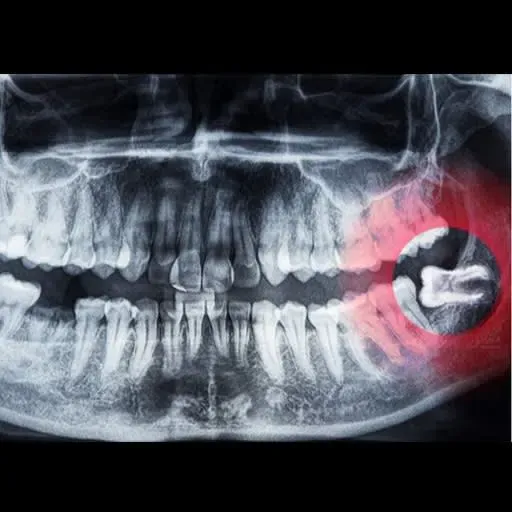

• Impaction – when there's not enough space at the back of the jaw for a wisdom tooth to erupt from the gum properly, it can become trapped (impacted) and may push into the neighbouring teeth, which can cause discomfort or pain.

The removal of wisdom teeth can be completed in the chair at our practice using local anaesthetic, IV sedation or in hospital under general anaesthetic. If you're having a wisdom teeth consultation at EVP Dental, we'll first take an x-ray of your mouth to determine whether extraction is necessary and to help us plan your treatment.

The upper wisdom teeth are generally the easiest to remove, which may not be any more complex than a general extraction. Lower wisdom teeth or teeth that are deeply impacted or hidden underneath the gums can be more difficult to remove. These may require oral surgery.